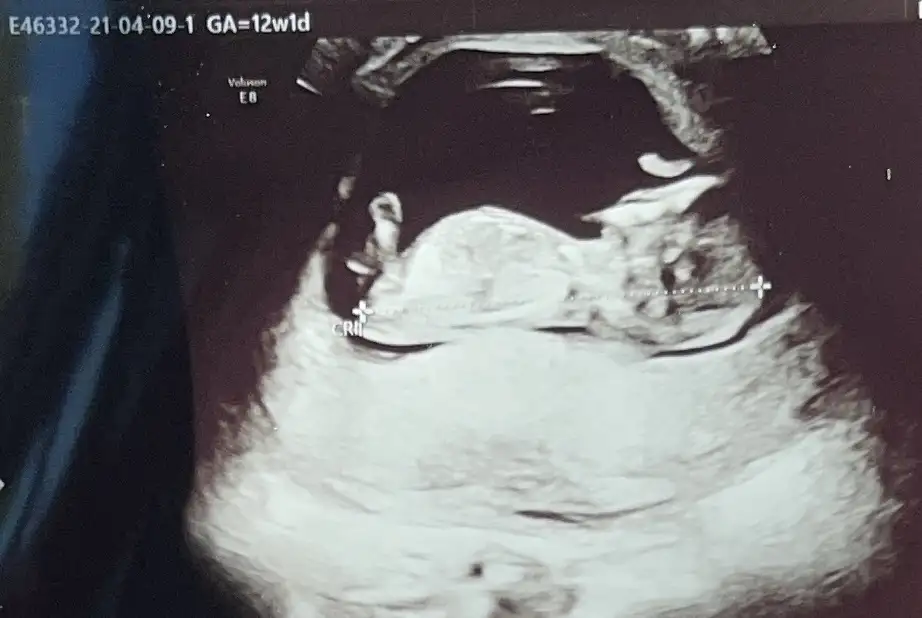

Ikra meyra 12+3 ama dr göremedi net sizin tahmininiz var mıı

Eklentiler

• AA2EEB5F-114E-46A9-8A68-90EF4DA55D4A.webp

24,6 KB · Görüntüleme: 61

• 974C7258-749E-4A4A-87AE-CDDC3E9370B7.webp

23,6 KB · Görüntüleme: 51

• B1506CB2-3341-4227-B8F3-C06147BE779C.webp

13,9 KB · Görüntüleme: 54